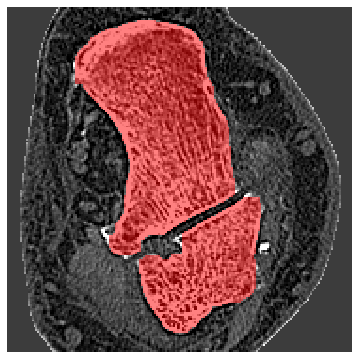

Bone Segmentation